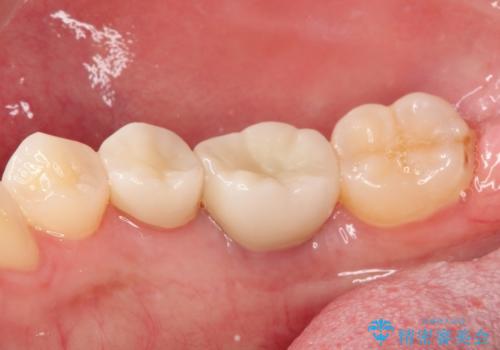

見た目では問題がなさそうでも、レントゲン撮影・診査を行うと状態が悪くなっていることがあります。